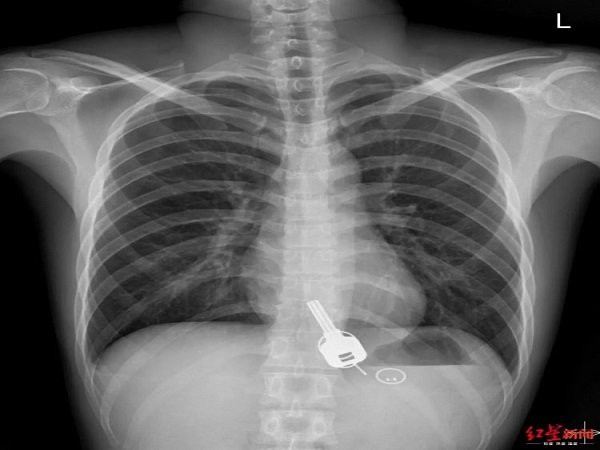

மருத்துவர்கள் எக்ஸ்ரே எடுத்து பார்த்து சாவியின் நிலையை கண்டறிந்து அறுவை சிகிச்சை செய்து அதை நீக்கி உள்ளனர். மேலும் இந்த சாவி அந்த பையனின் குடலை கிழித்து உள்ளதாகவும் உணஙுக்குழாயையும் கிழித்து உள்ளதாகவும் மருத்துவர்கள் கூறுகின்றனர். எப்படியோ மருத்துவர்கள் சாவியை எடுத்துவிட்டனர்.